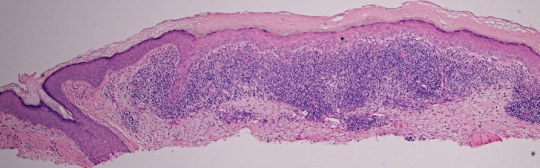

VA1: Left Forearm, Actinic Keratosis